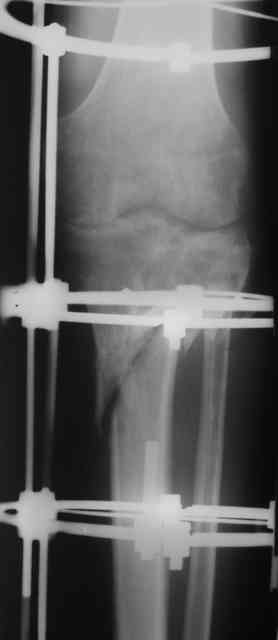

Р-граммы и фото за 4.05.2007 - 7-е сутки после операции.

Ход операции - линейным разрезом по передней поверхности голени обнажена зона ложного сустава большеберцовой кости. От кости отсепарованы медиально м/ткани. Из зоны ложного сустава убраны рубцовые ткани, мобилизован дистальный отломок. По передней поверхности удалены два осколка, связанных грануляциями. Произведено удаление грануляционной ткани из проксимального отломка (на вид сине-серого цвета), "чистого" гноя не было. Затем произведено наложение аппарата и репозиция отломков. По передне-медиальной поверхности образовался дефект до 4х2х2 см + полость в проксимальном отломке. Удаленные осколки очищены от грануляций, уложены в место дефекта, зажаты между отломками. После иссечения раны по передней поверхности, находящейся рядом с операционной раной, последняя ушита с большим натяжением.

Перелом мыщелка сросся. Проксимальный отломок очень порозный.